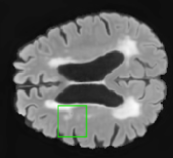

In order to analyze qualitatively the results of our generator, we extract slices with different WMHs loads, Table 4 shows the reconstruction results for three different levels of loads. As we can see in the first row, both methods produce a similar response in regions with a low load of lesions, it can be observed that generated images are similar to the real FLAIR images in the left, and these not present evident structural distortions. However, it can be noted images exhibit blurred effects, which can be due to L2 based optimization, more complex generative networks with adversarial loss optimization as GANs tend to eliminate blurred effect but at the expense to produce structural distortions. In the application presented in this work it is important to preserve the structural information, thus, our L2 based optimization present a good balance between preserve structural information and blurred effects. In the second and third column, it can be observed the performance of both methods when facing the presence of lesions, as can be seen, both methods have a good response to large and contiguous lesions. It also can be noted both methods tend to produce poor performance in small and diffuse WMHs marked in red, note, these lesion do not exhibit identifiable patterns in T1 images, however it can be seen that our proposed method is more sensitive to these patterns which enable to highlight some small regions as those marked in green.

FLAIR T1 Offline synthesis Proposal

[Uncaptioned image] [Uncaptioned image] [Uncaptioned image] [Uncaptioned image]

Table 4: Results of Generation for all the proposed methods,